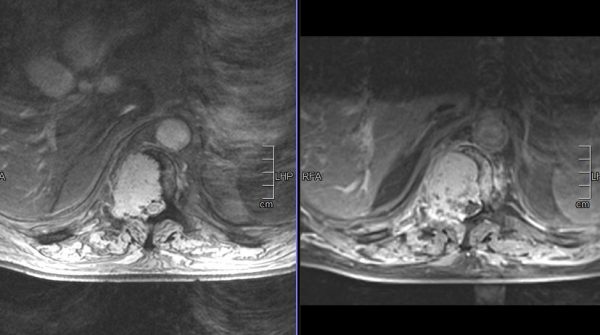

Παράδειγμα εξωσκληρίδιου όγκου: Ασθενής Άρρεν, 73 ετών, με γνωστή μεταστατική μάζα στον Θ10 σπόνδυλο, η οποίοα προκαλεί σημαντική στένωση του σπονδυλικού σωλήνα και πίεση επί του νωτιαίου μυελού. Διενεργήθη αποσυμπίεση του νωτιαίου μυελού και διαδερμική σπονδυλοδεσία/σπονδυλοπλαστική Θ9-Θ10. Μετεγχειρητικά ο ασθενής ανέφερε σημαντική πίεση του άλγους του και σημαντική βελτίωση της βάδισης.

(Προσωπικό Αρχείο Νευροχειρουργού Π. Σταυρινού)